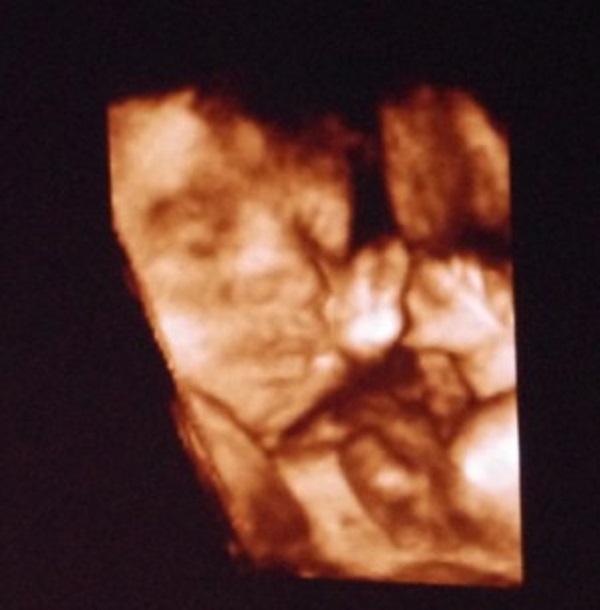

解读25周四维彩超报告单,各项参数含义一网打尽

灌篮高手

普通人可以通过四维彩超报告单上各项数值的相对应的具体含义来进行解读,四维彩超检查是孕妇在怀孕过程当中...